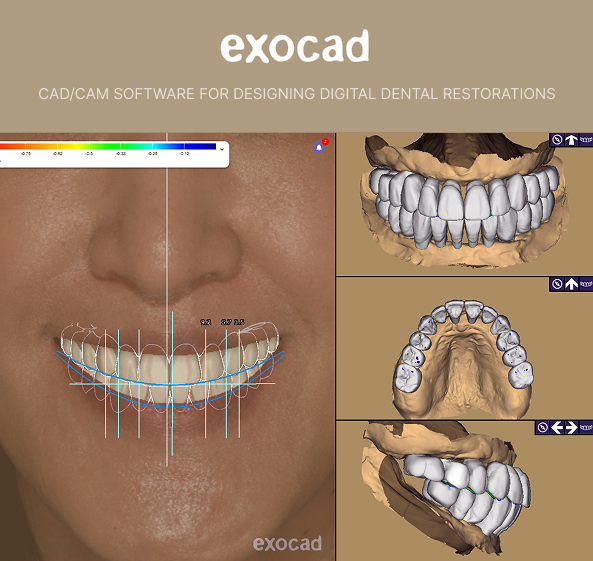

Digital smile design is available and can help you visualize the potential outcome of treatment. This process involves using digital photos and a scan of your teeth to create virtual images showing how a proposed treatment could change the appearance of your teeth.

Our state-of-the-art technology includes the latest smile design software and an on-site milling machine that fabricates precision-made, aesthetically beautiful, and durable restorations. Every treatment is designed to provide a natural, balanced, and beautiful smile, delivered by a team that takes pride in delivering personalized and compassionate dental care.